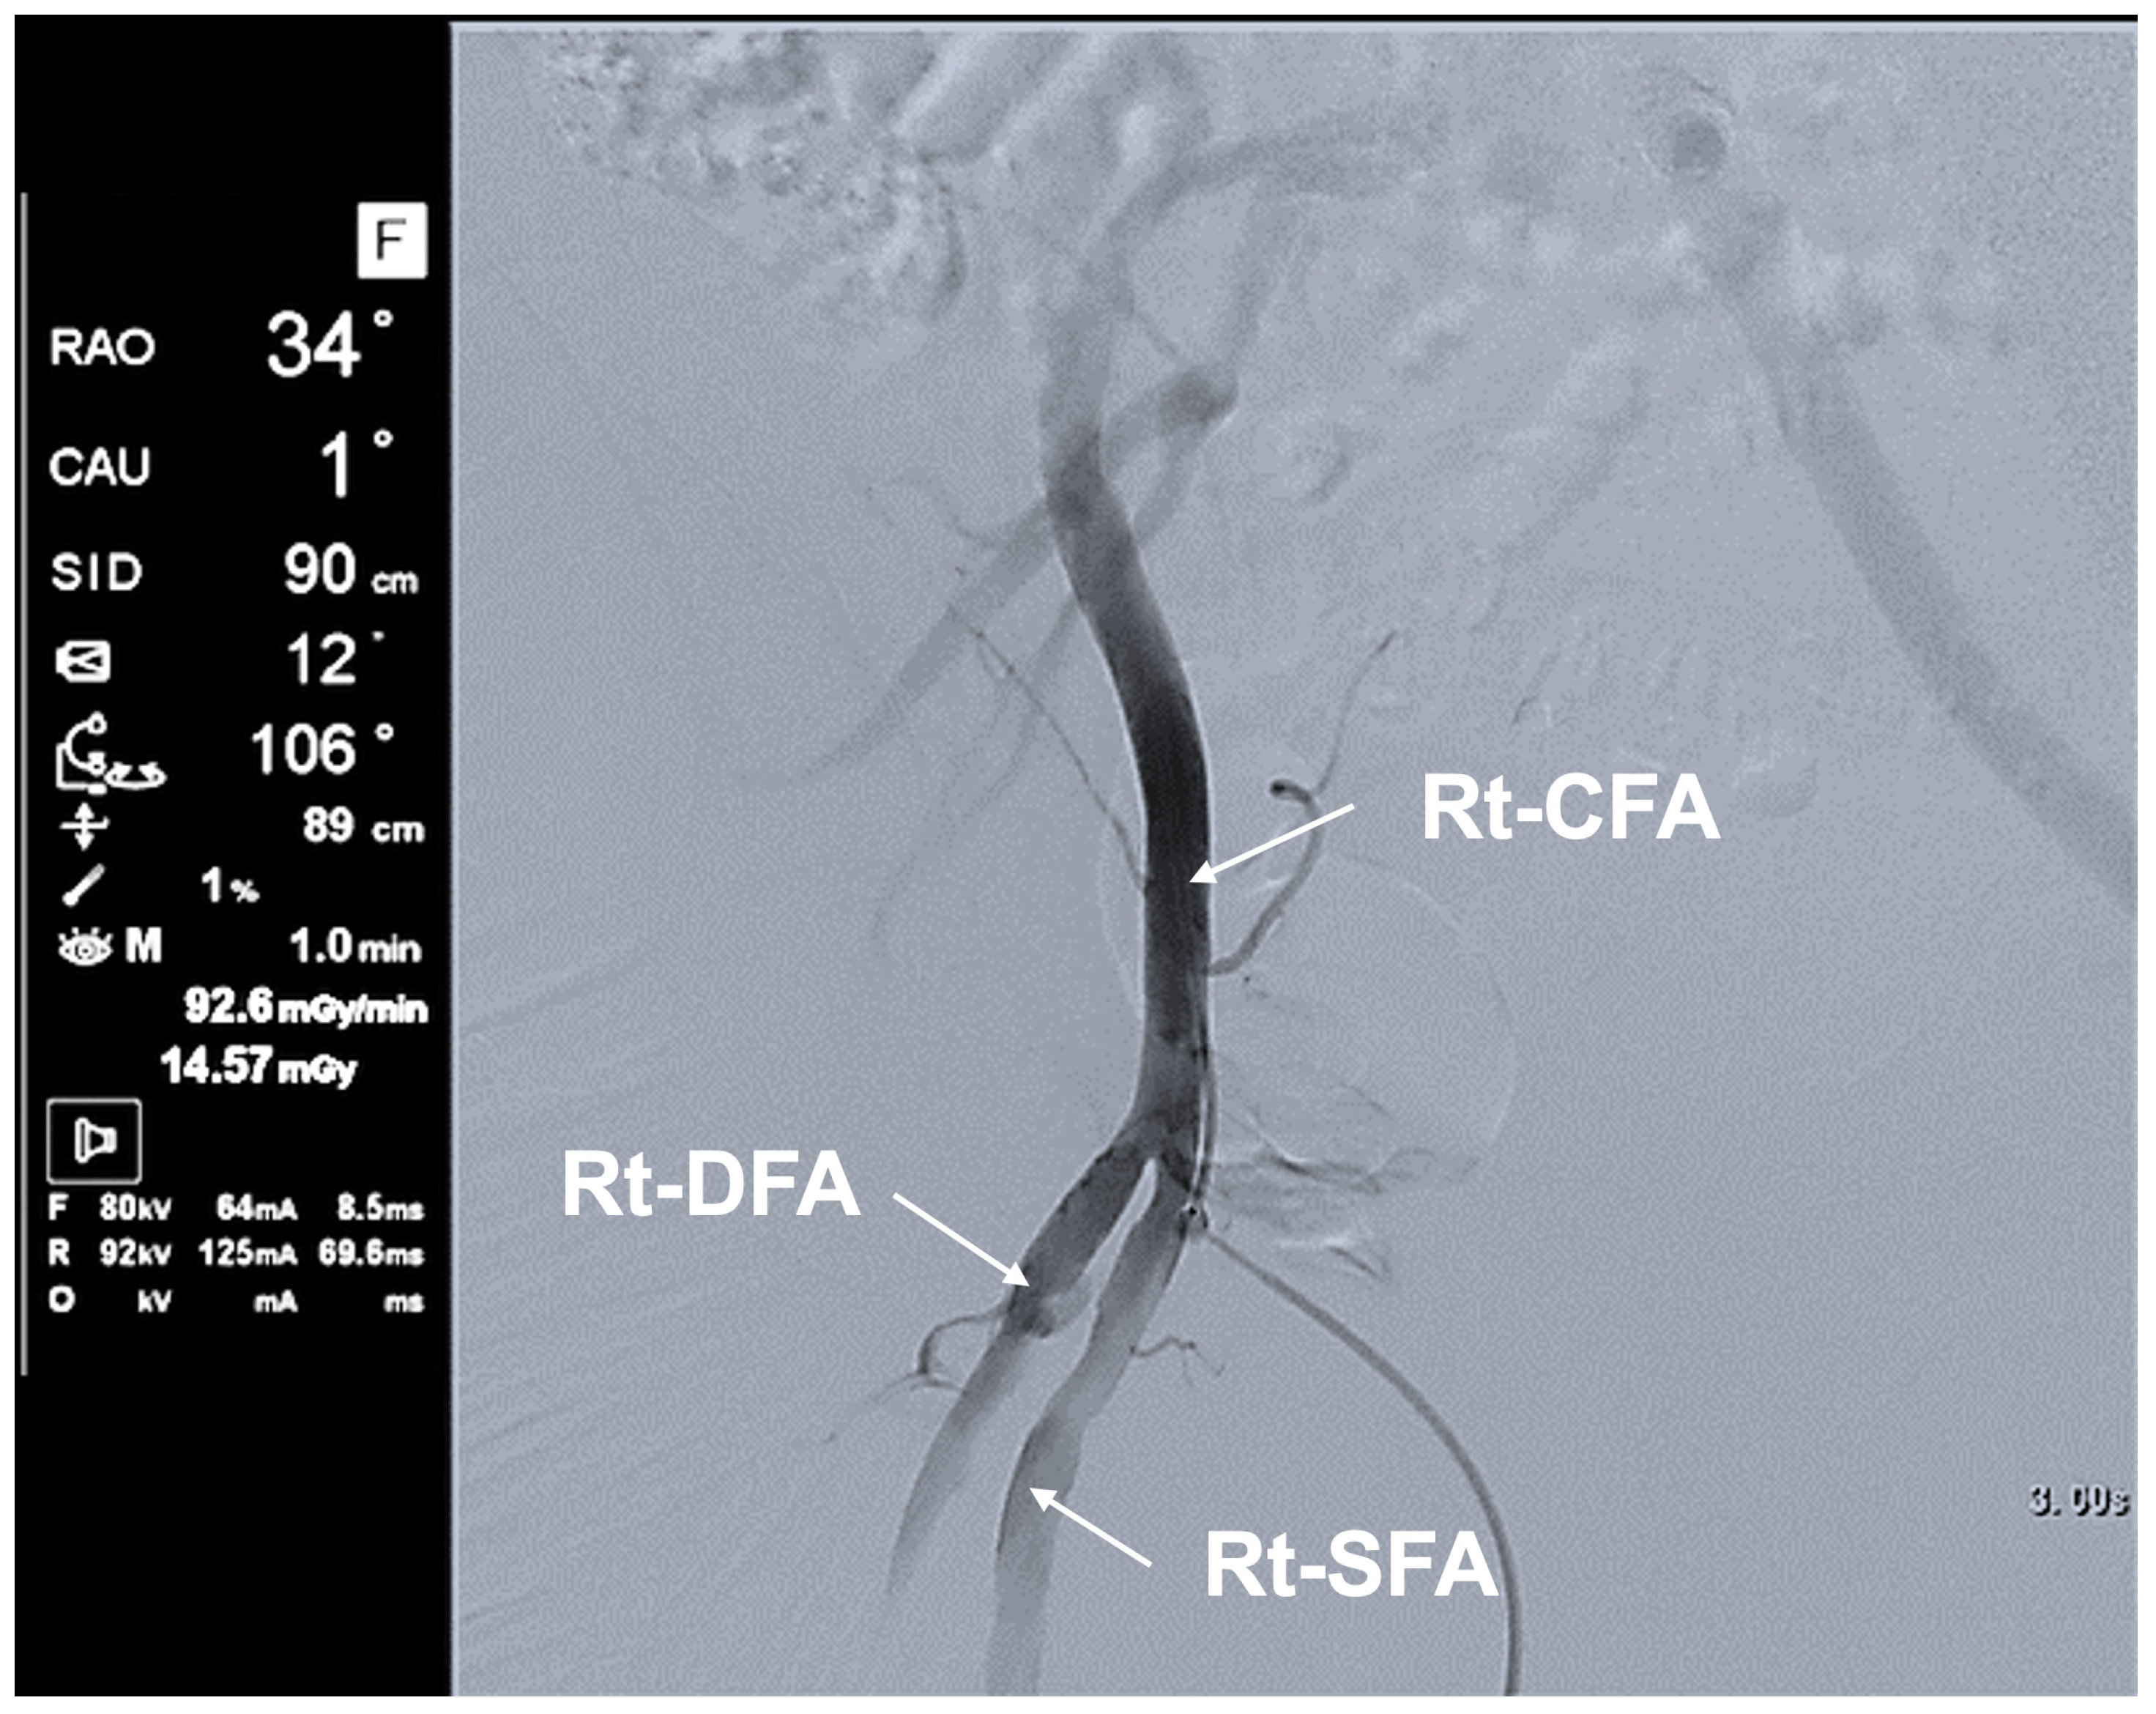

3.3.2. Typical Scene 2 (Case 5)

| Typical Scene No. | Case No. | DSA Site | X-Ray Projection | FPD Size (inch) | SID (cm) | Ka,r (mGy) | Table Height (cm) | Cervical Unprotected Dose Rate (mSv/h) | Chest Unprotected Dose Rate (mSv/h) | Cervical/Chest Unprotected Dose Rate Ratio |

|---|---|---|---|---|---|---|---|---|---|---|

| 1 | 5 | Rt FAG | Frontal—RAO 16°, Caudal 1° | 12 | 90 | 62.8 | 79 | 5.16 | 11.75 | 0.44 |

| 2 | 5 | Rt FAG | Frontal—LAO 20°, Cranial 0° | 12 | 90 | 70.4 | 87 | 11.29 | 35.27 | 0.32 |